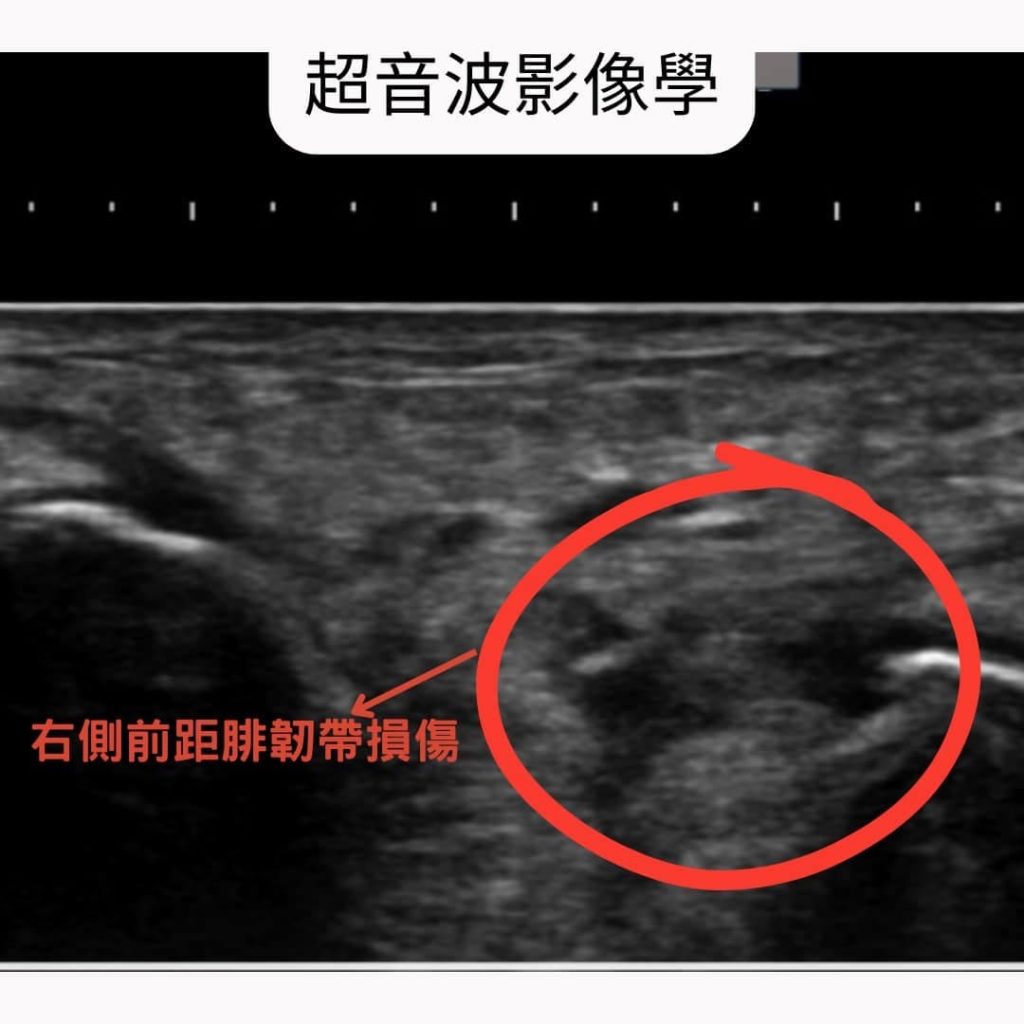

▪️影像檢查

超音波檢查也顯示蘇小姐右腳踝的外側韌帶有慢性扭傷的問題。而進一步的磁振造影檢查,也發現踝關節外側韌帶(圖示: 前距腓韌帶與跟腓韌帶)都有慢性損傷的問題。